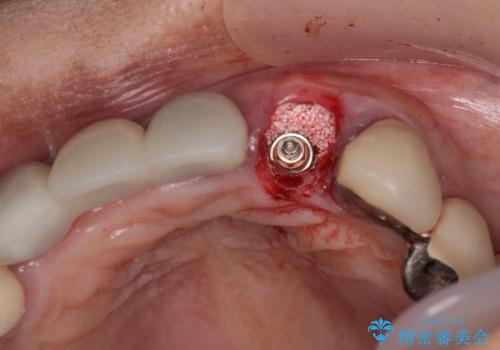

歯根周辺の骨や歯肉の状態は良く、抜歯して速やかにインプラントを埋入し、即日で仮歯を装着するプランにて治療を行うこととしました。

事前に仮歯の型取りをして用意をしていたため、インプラント埋入後に速やかに仮歯を装着しました。

インプラントの安定度も高く、抜歯と埋入から2か月後にはオールセラミッククラウンを装着することができました。